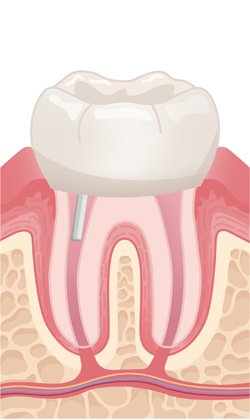

신경치료를 받지 않으면 치아를 발치해야 합니다.

신경치료를 한다고해서 이미 죽은 조직을 살릴 수는 없지만 신경치료를 통해 통증을 없애주고 염증이 치아 뿌리를 싸고 있는 뼈 조직으로 퍼지는 것을 막아줍니다.

이처럼 신경치료는 치아를 뽑지않고 치아의 형태와 기능을 최대한으로 오랫동안 사용할 수 있도록 보존하는 치료입니다.

약해진 치아를 보호하기 위해 맞춤 제작된 크라운을 씌워 강도와 기능을 회복시키며, 장기적으로 안전하게 사용하도록 마무리합니다.